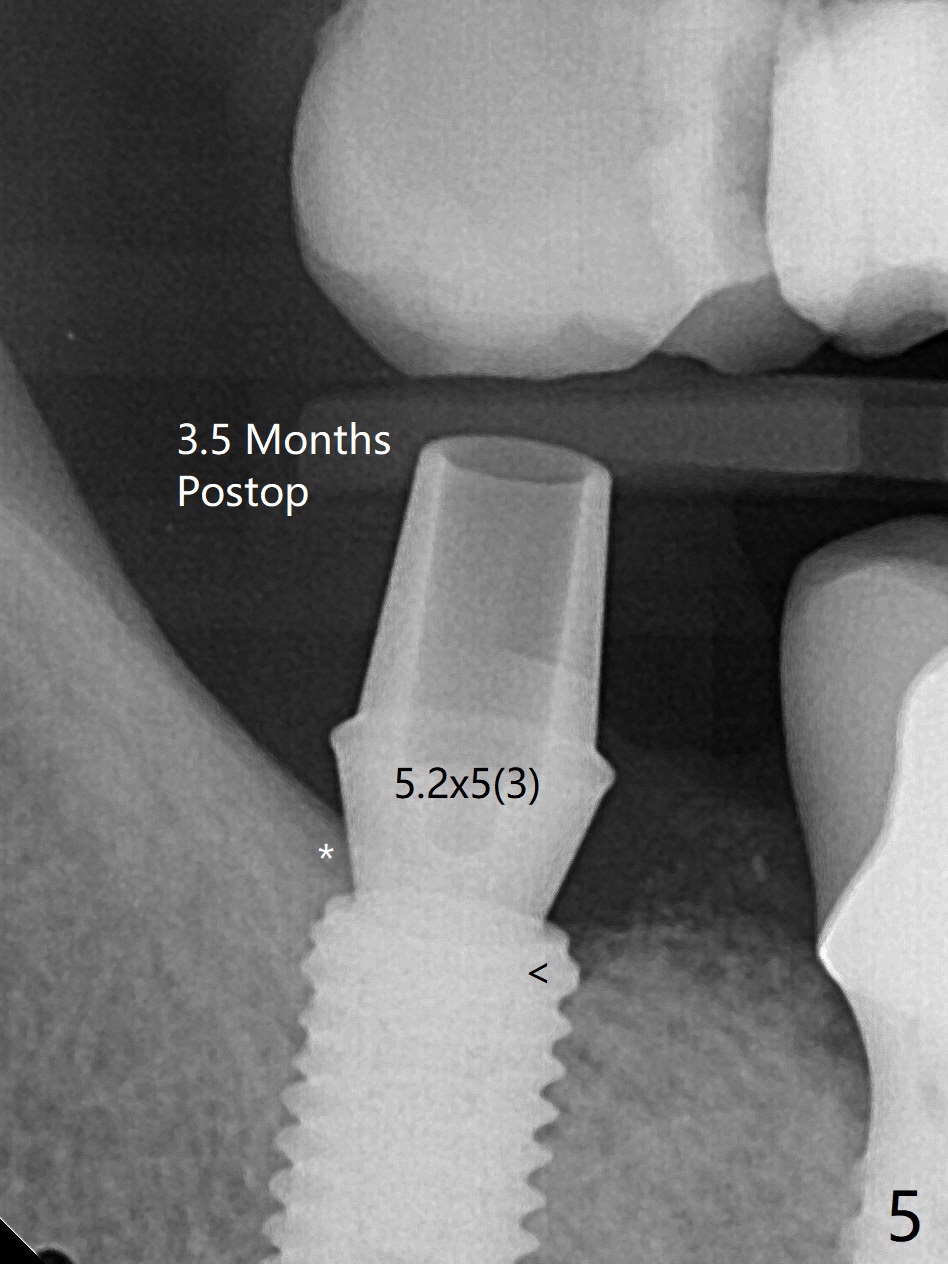

61岁女右下7导板钻洞,第一个钻头(环形钻)就有困难入位,部分磨去对合7近中腭侧牙尖(图一:*),钻头入位就好多了(图二:^,对比)。钻洞时发现骨质密度中等,所以最后钻头直径4.5毫米。不过无法用手植牙工具旋入植体,使用5.0毫米功螺纹钻头后,手工具就好用了,植体植入一定深度,扳手有空间插入,最后扭力30Ncm。第二个问题,当按照设计深度植入植体,用探针检查颊侧好像没有骨壁;加深大约0.5毫米(仿佛没有取到目的,颊侧骨板不明显)后,使用6毫米profile钻头,插入5.5x3毫米愈合基台(图二,三),在基台和颊侧牙龈之间植入异体骨粉,但愿帮助颊侧骨板再生。术后一周内敷料脱落,颊侧伤口愈合,好像骨粉没有流失。术后2.5月愈合基台脱落,换至小号基台(4向毫米),仍旧疼痛,休息2分钟,手拧紧,拍摄根尖片,仿佛就位(图四)。准备一周后调换稍微大,例如,4.8毫米基台。术后3.5个月,5.2毫米基台好像没有就位(图五:<),可能与远中牙槽嵴接触(*)。小一号基台仿佛就位(图六),与远中牙槽嵴无接触。术后4个月粘固后基台螺丝拧紧30Ncm。术后8个月,也就是粘固后4个月,牙槽嵴似乎试图覆盖植体平台(图七:箭头)。